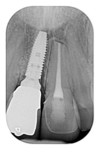

Il s'agit d'un cas d'une chute avec expulsion de l'incisive centrale droite et fracture de l'incisive centrale gauche.

Un implant avec greffe osseuse a été posé en site de l'incisive droite et une facette sur dent dévitalisée sur l'incisive gauche.

La réalisation a été faite par un laboratoire meilleur ouvrier de France.